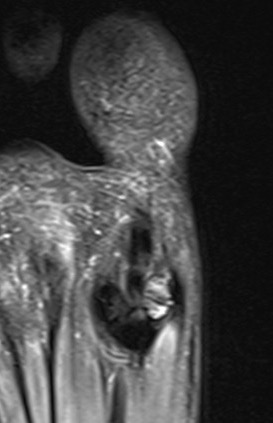

CT demonstrates irregular borders consistent with fracture of tibial sesamoid

Edema on T2 MRI indicates likely acute fracture

Sesamoid Avascular necrosis

Xray

Enlarged / deformed / sclerotic with mottling / fragmentation